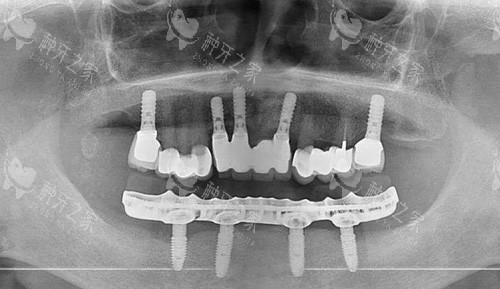

全口种植牙前后

全口种植

全口种植牙解析图